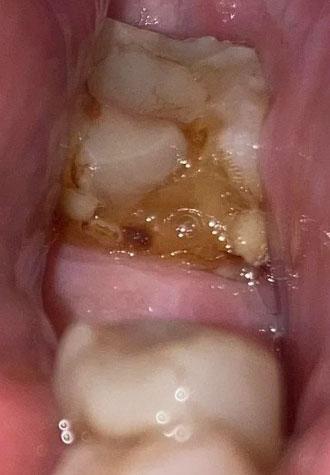

The image shows a full lower arch view with visible multiple carious lesions, plaque accumulation, and structural enamel damage. Several posterior teeth present brown cavitated areas indicating active dental decay. The lower anterior teeth also show crowding and tartar buildup.

This condition appears progressive and requires immediate dental evaluation to prevent further complications.